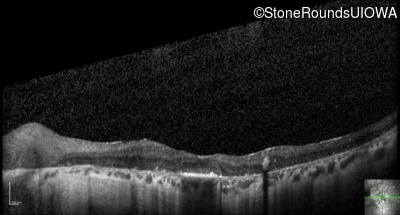

Visit at age: 36 years

Optical Coherence Tomography - Right - 20/80

Exemplar / OCT Stack

OCT Stack